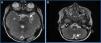

Se presenta el caso de un varón de 2 años que consulta de forma urgente en el hospital de zona por crisis convulsiva (crisis parcial compleja), estando previamente asintomático. Se inicia estudio con prueba de imagen y, ante la sospecha de lesión ocupante de espacio cerebral, fue remitido al centro de referencia. En las pruebas de imagen realizadas, se detectó afectación tumoral maligna y diseminada por las cubiertas meníngeas de todo el neuroeje, y una lesión principal a nivel intracerebral (tumor retroclinoideo izquierdo con diseminación meníngea difusa) (fig. 1).

A) Lesión principal. Sospecha de tumor primario. Tumoración sólida, de 30 mm (CC)×27 mm (AP)×20 mm (T), en la vertiente izquierda de la cisterna prepontina. B) Diseminación tumoral meníngea. Realce leptomeníngeo seudonular grosero que se extiende por valles y cisuras de Silvio, cisternas interpeduncular, cuadrigeminal, prequiasmática, receso pineal y receso anterior superficie anterior del bulbo.